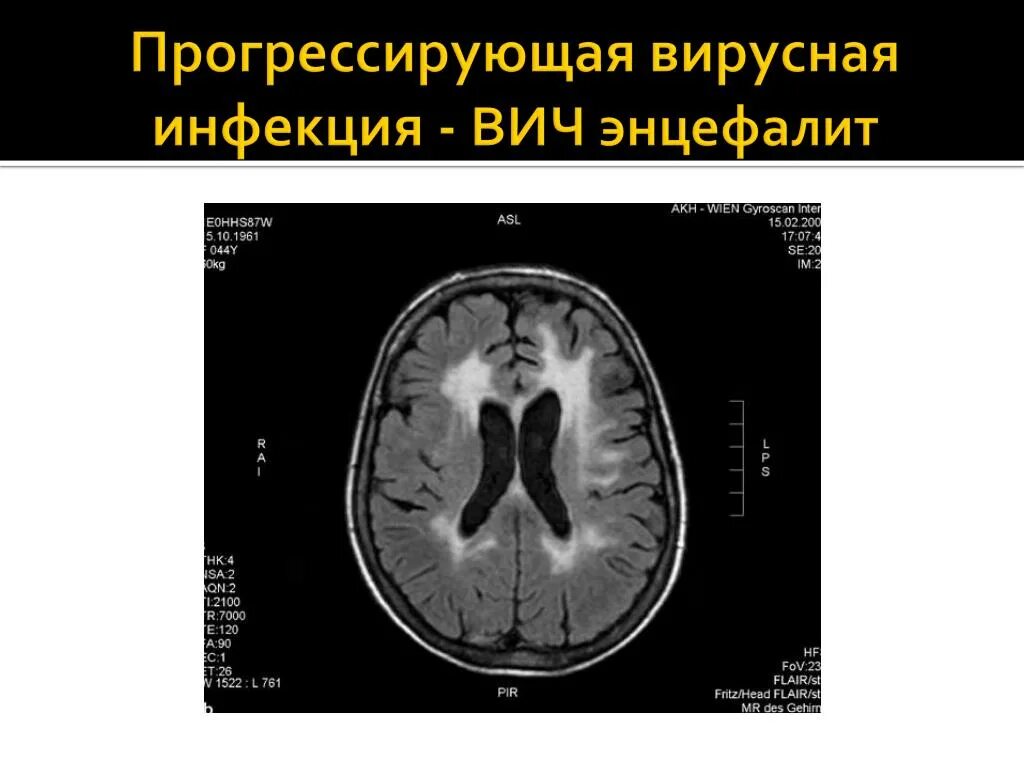

Энцефалит головного мозга симптомы у взрослых